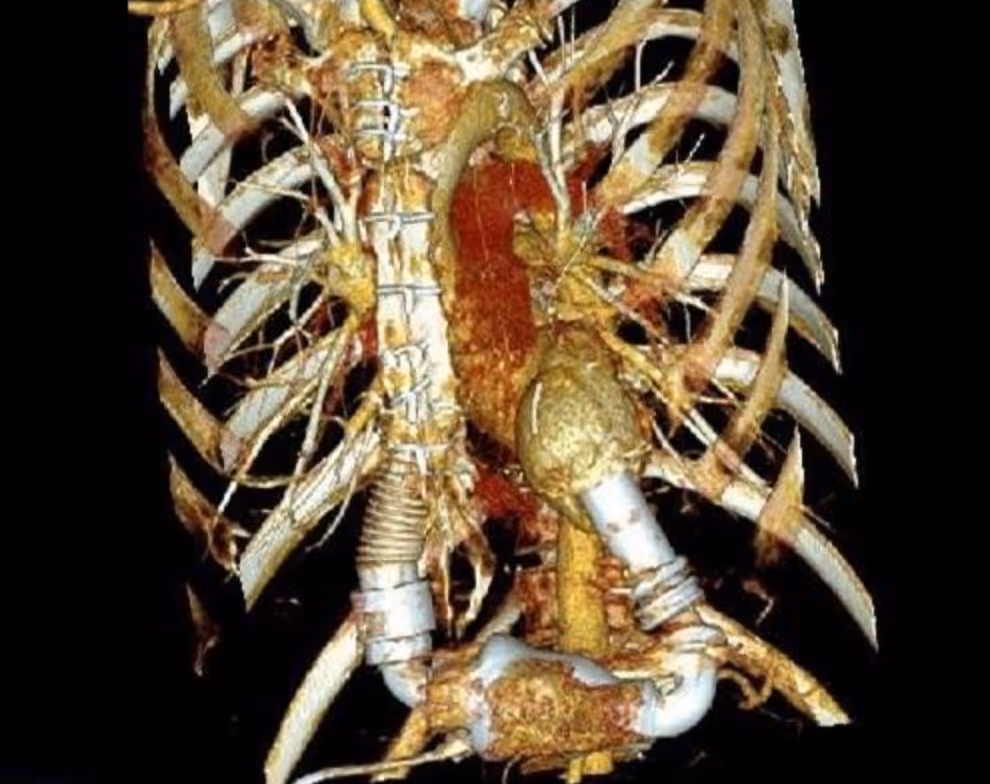

Patient with a Stanford type A aortic dissection

2021-03-08

in

Clinical Cases